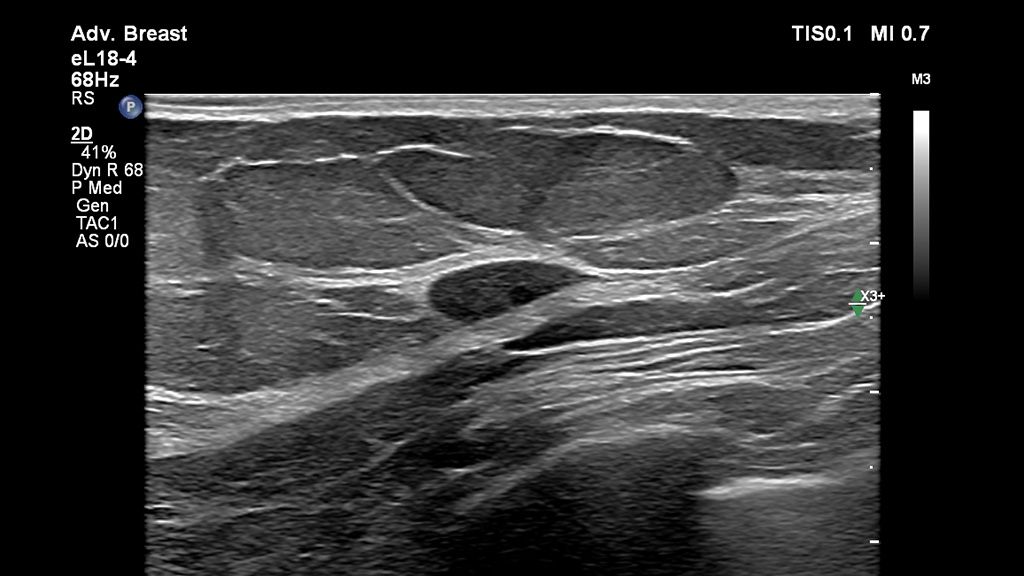

• eL18-4 with 2D Imaging

eL 18-4 transducer with 2D imaging

• The eL18-4 and mL26-8 transducers provide excellent B-mode imaging, needle visualization that enhances the needle tip, strain and shear wave elastography and MicroFlow imaging.